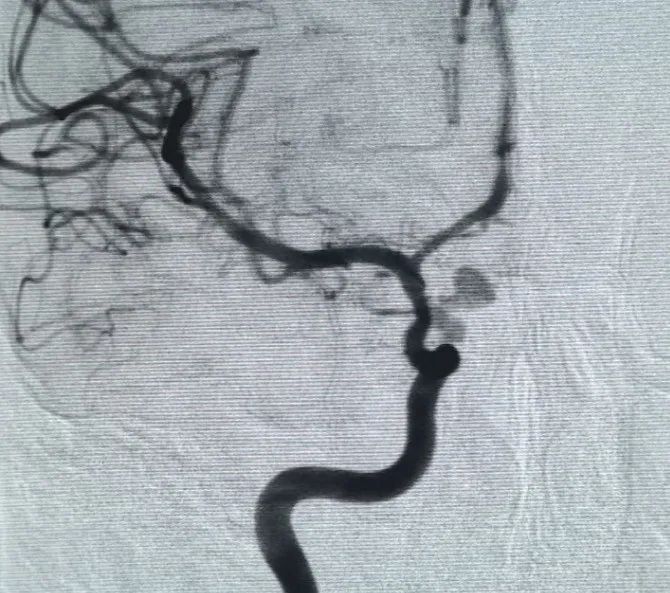

Um Perfiller®3mm × 6 cm bobina expansível e um Perfiller®3mm × 2 cm bobina expansível foram então colocados para completar a oclusão do pescoço. Posteriormente, uma Nuva®Desviador de fluxo (TJED-D-5.0-16) foi entregue e implantado no pescoço do aneurisma. A angiografia de seguimento tanto na visão anteroposterior quanto na lateral confirmou excelente cobertura, boa aposição da parede e clara radiopacidade, com acentuada estagnação do contraste.

O procedimento foi realizado sem complicações, e o paciente recuperou-se sem déficits neurológicos.